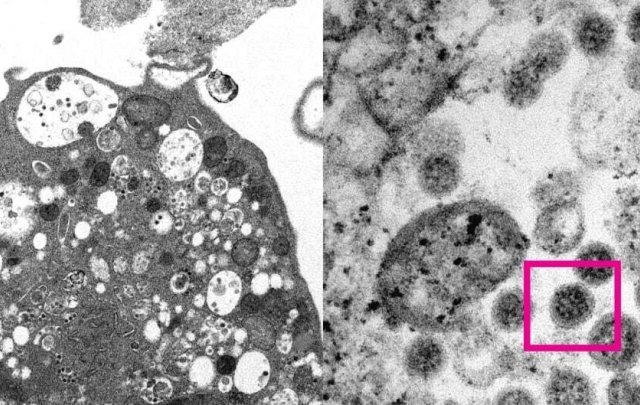

CNN ngày 18/2 dẫn nghiên cứu mới của chuyên gia Kei Sato (Nhật Bản) nêu rõ, không nên xem BA.2 là một nhánh của Omicron...

Chuyên gia: Biến thể phụ có thể tạo làn sóng lây nhiễm song song với Omicron

Theo nhà khoa học Nam Phi, biến thể phụ được gọi là BA.2 đang lây lan nhanh chóng và có thể gây ra làn sóng...